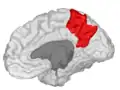

Precuneus of left cerebral hemisphere (shown in red).

Medial surface of left cerebral hemisphere. (Precuneus visible at top left.)- Medial surface of left cerebral hemisphere. (Precuneus colored in red.)